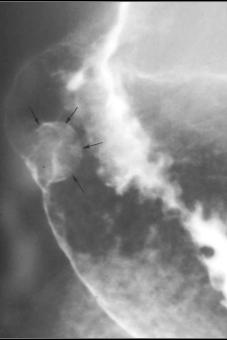

Aspect polypoide

intraluminal d'une tumeur epithelial . Sa bord est

irreguliere, polyglobulaire et sessile |